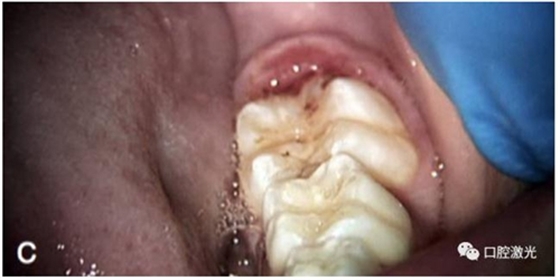

術(shù)后即刻

在選擇口腔激光對盲袋進(jìn)行切除時,任何波長的激光都可以做到。但由于二氧化碳激光屬于非接觸操作,加上磨牙位置的原因,操作相對復(fù)雜,不推薦使用。如果選擇鉺激光,注意不得接觸到牙釉質(zhì),否則會造成牙體硬組織的切除。另外,鉺激光由于對止血無作用,因此使用中存在一些不利因素。但在麻醉方面,鉺激光可以使用表麻,如果選擇其他激光則通常需要進(jìn)行注射局部麻醉。